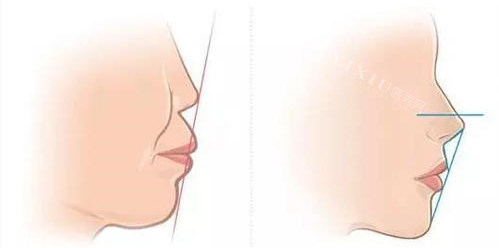

隐形矫正与美学正畸:提供包括陶瓷托槽、隐形矫正等多种正畸方案,针对牙列拥挤、牙列稀疏、龅牙、地包天等各类错颌畸形进行个性化矫正。

牙齿矫正:传统金属托槽矫正约1.2-1.8万元;陶瓷托槽矫正约1.8-2.5万元;隐形矫正(隐适美等)约2.5-4.5万元。